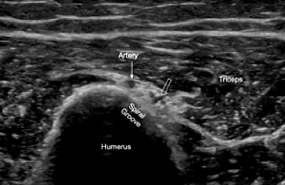

우리 위팔뼈에는

요골신경이 지나가는 특별한 길이 있습니다.

**'나선 고랑(spiral groove)'이라고 하는데요.

이름 그대로 나선형,

사선으로 파인 이 길을 따라서

'요골신경'이 지나갑니다.

여기를 지나갈 때

신경 위쪽에는

말캉한 근육이 있는데요.

신경 아래쪽에는

딱딱한 뼈만 있고 별다른 쿠션이 없습니다.